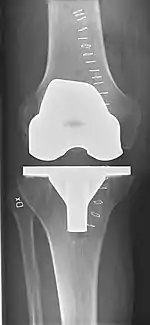

Knee replacement surgery can be performed as a partial or a total knee replacement.[3] In general, the surgery consists of replacing the diseased or damaged joint surfaces of the knee with metal and plastic components shaped to allow continued motion of the knee.

Technique

The surgery involves exposure of the front of the knee, with detachment of part of the quadriceps muscle (vastus medialis) from the patella. The patella is displaced to one side of the joint, allowing exposure of the distal end of the femur and the proximal end of the tibia. The ends of these bones then are cut accurately to shape, using cutting guides oriented to the long axis of the bones. The cartilages and the anterior cruciate ligament are removed; the posterior cruciate ligament also may be removed but the tibial and fibular collateral ligaments are preserved.[18] Whether the posterior cruciate ligament is removed or preserved depends on the type of implant used, although there appears to be no clear difference in knee function or range of motion favoring either approach.[18] Metal components are then impacted onto the bone or fixed using polymethylmethacrylate (PMMA) cement. Alternative techniques exist that affix the implant without cement. These cement-less techniques may involve osseointegration, including porous metal prostheses. Finally, stability and range of motion are checked, followed by irrigation, hemostasis, placement of hemovacs, and closure.[19]

Femoral replacement

A round-ended implant is used for the femur, mimicking the natural shape of the joint. On the tibia the component is flat, although it sometimes has a stem that goes down inside the bone for further stability. A flattened or slightly dished high-density polyethylene surface is then inserted onto the tibial component so the weight is transferred metal to plastic, not metal to metal. During the operation any deformities must be corrected, and the ligaments balanced so the knee has a good range of movement, and is stable and aligned. In some cases the articular surface of the patella also is removed and replaced by a polyethylene button cemented to the posterior surface of the patella. In other cases, the patella is replaced unaltered.